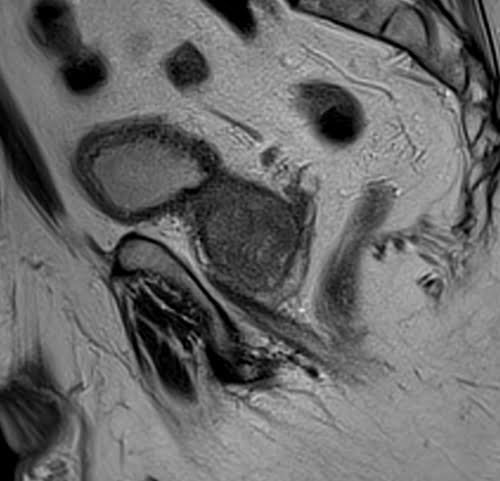

Prostate mri T2 sagittal high resolution images